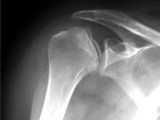

AVN-humerus

AVN-humerus